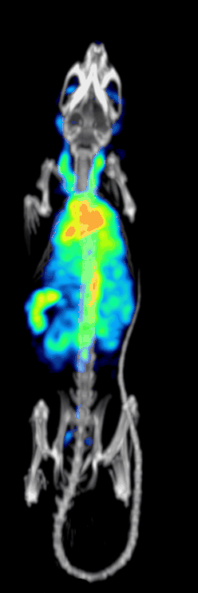

Preclinical or small-animal Single Photon Emission Computed Tomography (SPECT) is a radionuclide based molecular imaging modality for small laboratory animals[1] (e.g. mice and rats). Although SPECT is a well-established imaging technique that is already for decades in use for clinical application, the limited resolution of clinical SPECT (~10 mm) stimulated the development of dedicated small animal SPECT systems with sub-mm resolution. Unlike in clinics, preclinical SPECT outperforms preclinical coincidence PET in terms of resolution (best spatial resolution of SPECT - 0.25mm,[2] PET ≈ 1 mm[3][4] ) and, at the same time, allows to perform fast dynamic imaging of animals (less than 15s time frames[5]).

SPECT imaging requires administration of small quantities of γ-emitting radiolabeled molecules (commonly called "tracers") into the animal prior to the image acquisition. These tracers are biochemically designed in such a way that they accumulate at target locations in the body. The radiation emitted by the tracer molecules (single γ-photons) can be detected by gamma detectors and, after image reconstruction, results in a 3-dimensional image of the tracer distribution within the animal. Some key radioactive isotopes used in preclinical SPECT are 99mTc, 123I, 125I , 131I , 111In, 67Ga and 201Tl.

Preclinical SPECT plays an important role in multiple areas of translational research[6] where SPECT can be used for non-invasive imaging of radiolabeled molecules, including antibodies, peptides, and nanoparticles. Among major areas of its applications are oncology, neurology, psychiatry, cardiology, orthopedics, pharmacology and internal medicine.